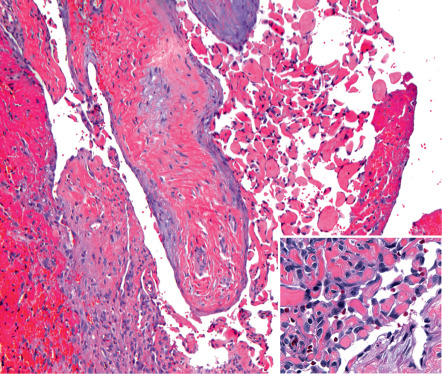

Intravascular examples may be limited to the confines of a single thin-walled vein or may arise, often multifocally, within pre-existing vascular lesions such as venous malformations, glomuvenous malformations, spindle cell hemangiomas, and pyogenic granulomas ( Fig. 114.2 ). Foci of intravascular PEH are extremely common in venous malformations and serve to distinguish these low-flow lesions from high-flow arteriovenous malformations. Rarely, the involved vessel wall is ruptured, allowing the proliferative vascular process to spill out into the adjacent stroma. Extravascular examples that on serial sectioning show no evidence of a surrounding blood vessel wall may have arisen within an organizing hematoma .

Early lesions show growth of endothelial sprouts into fibrinous thrombus material, dividing it into papillary fronds lined by a single layer of plump endothelial cells with minimal mitotic activity and no significant cytologic atypia ( Fig. 114.2 , inset). The early fibrin cores of the papillae become collagenized and hyalinized with time, and the endothelial lining becomes thin and attenuated. Lesional papillae may fuse to form an anastomosing meshwork of vessels separated by connective tissue stroma that mimics angiosarcoma. However, the relatively high mitotic rate, striking pleomorphism, and necrosis that characterize angiosarcoma are lacking .